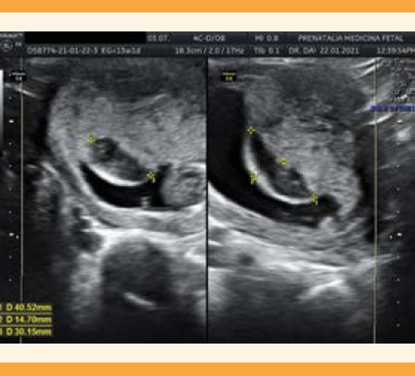

De manera rutinaria se ofreció, a quienes la aceptaron, la exploración estructural vaginal temprana. La protuberancia corial se definió como: cualquier estructura convexa e irregular que protruyera de la superficie coriodecidual dentro del saco gestacional del primer trimestre y que se documentara ausencia de flujo sanguíneo nutricio mediante Doppler color (Figuras 1 a 4).

Figura 1 Imagen de la protuberancia corial diagnosticada antes del tamizaje del primer trimestre, con persistencia después de las 13 semanas.